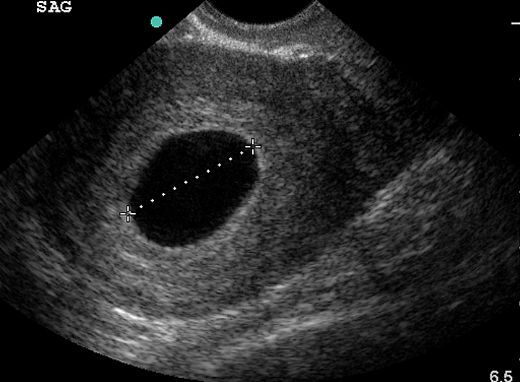

7 Haftalık Gebelikte (Hamilelikte) Kanama Nedenleri?

3 Aylık Gebelikte (Hamilelikte) Kanama Nedenleri?